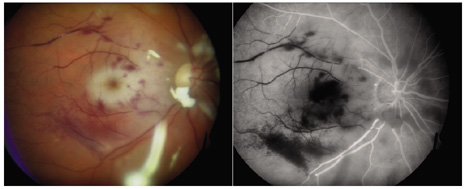

ACUTE-ONSET POSTOPERATIVE ENDOPHTHALMITIS This category of endophthalmitis occurs within 6 weeks of intraocular surgery. It can occur from a variety of intraocular surgical procedures ranging from radial keratotomy to cataract surgery. Pain is a frequent but inconsistent symptom and was absent in 25% of EVS patients. The visual loss is generally greater than that expected during the usual postoperative course. Organisms most frequently involved are the coagulase-negative staphylococci, S. aureus, Streptococcus species, and gram-negative organisms. DELAYED-ONSET OR CHRONIC POSTOPERATIVE ENDOPHTHALMITIS In this endophthalmitis category, patients may present weeks to months after cataract extraction, often with mild-to-moderate inflammatory signs and a chronic indolent course.16,94 P. acnes, a gram-positive, anaerobic pleomorphic rod, is a common causative organism in this category. The clinical P. acnes syndrome of delayed-onset pseudophakic endophthalmitis, first described by Meisler and associates94 in 1986, typically includes granulomatous inflammation with large keratic precipitates (Fig. 6) and a white intracapsular plaque that has been shown to be composed of organisms mixed with residual lens cortex. When infection with this slow-growing organism is suspected, anaerobic cultures of both the aqueous and vitreous should be obtained and held at least 2 weeks. In a review of 19 patients with delayed-onset pseudophakic endophthalmitis (defined as those cases diagnosed 6 weeks or more after cataract surgery and excluding filtering bleb-associated cases), four different etiologic organisms were isolated.13 These included Propionibacterium species (63%), Candida parapsilosis (16%), Staphylococcus epidermidis (16%), and Corynebacterium species (5%).11 Endophthalmitis due to Mycobacterium chelonae may also present as delayed-onset or chronic postoperative endophthalmitis with white opacities in the lens capsule or anterior vitreous; such cases may be initially misdiagnosed as P. acnes.95 In the initial management of P. acnes pseudophakic endophthalmitis with a white intracapsular plaque, a PPV and a central capsulectomy together with intravitreal antibiotics (intravitreal corticosteroids are optional) is generally recommended.14–16 Selective removal of the observed white plaque using the vitrectomy probe assisted by scleral depression may reduce the frequency of recurrent infection (Figs. 4A and 4B). Vancomycin 1 mg has been the initial antibiotic of choice because of its broad spectrum of coverage against gram-positive organisms and because it can be injected into the remaining capsular bag after the vitrectomy.14–16 Vancomycin has been recommended over other antibiotics, but vancomycin's activity is diminished under anaerobic conditions. Isolates of P. acnes are also sensitive to methicillin, cefazolin, and clindamycin. In clinically suspected fungal infections characterized by fluffy white vitreous infiltrates (Fig. 7), injection of intravitreal amphotericin B 5 μg should be considered. If the initial treatment approach does not eliminate the infection, total capsulectomy and intraocular lens removal or exchange can be considered in this staged approach.96,97 Voriconazole or miconazole can be considered for amphotericin B–resistant organisms.98–101 Other categories of delayed-onset endophthalmitis include cases associated with suture removal or severe bacterial keratitis, or exposed glaucoma drainage devices.102 Sutures for scleral fixation of intraocular lens haptics may erode through the conjunctiva and allow organisms entry into the eye.103 CONJUNCTIVAL FILTERING BLEB-ASSOCIATED ENDOPHTHALMITIS This category of endophthalmitis is similar to acute postoperative endophthalmitis in that these patients manifest a sudden onset of pain, visual loss, conjunctival congestion, purulent bleb involvement, and the typical diagnostic features of acute-onset endophthalmitis (Fig. 8).10,11,104 Risk factors for this category of endophthalmitis include a history of conjunctivitis, contaminated topical glaucoma medications, the use of contact lenses, and inferior filtering bleb.10,104 The incidence of bleb-related endophthalmitis after a glaucoma-filtration procedure with mitomycin C may be higher than for trabeculectomy without antifibrotic agents.104 The organisms frequently involved in this type of endophthalmitis include streptococcal species8,71 and Hemophilus influenzae. Because of the frequency of these virulent organisms and the generally poor visual acuity outcomes, PPV and intraocular antibiotics are often considered as the initial approach for conjunctival filtering bleb-associated endophthalmitis. It is important to distinguish between a localized bleb infection (blebitis) and true endophthalmitis associated with an infected filtering bleb.11 The former category can be treated with intensive topical, subconjunctival, and possibly systemic antibiotics while the latter category can be treated in a manner similar to acute-onset postoperative endophthalmitis (Fig. 9). POSTTRAUMATIC ENDOPHTHALMITIS The visual outcomes after treatment of posttraumatic endophthalmitis are generally worse than the other endophthalmitis categories. In addition to vitreous infiltrates and hypopyon, other signs of posttraumatic endophthalmitis include exudate around foreign body and retinal periphlebitis (Fig. 10). In the National Eye Trauma System21 review of endophthalmitis after penetrating injuries with retained intraocular foreign bodies, 9 of 22 (40.9%) culture positive cases achieved 20/400 or better visual acuity. Either Bacillus or staphylococci species were isolated in 21 of these 22 (95%) culture-positive cases. Endophthalmitis was much less likely to develop in eyes with primary repair within 24 hours of the injury (10/287 or 3.5%) than in eyes with primary repair more than 24 hours after the injury (22/164 or 13.4%; p < 0.0001). Major reasons for the poor visual acuity outcomes in these cases are the marked structural damage to the eye resulting from the initial injury, the delay in the primary wound repair, and the greater virulence of the organisms commonly associated with the traumatic endophthalmitis. Bacillus species, most commonly B. cereus, are cultured from 28% to 46% of eyes with posttraumatic endophthalmitis.20,21,105 Bacillus species are ubiquitous, aerobic, gram-positive, spore-forming rods. Endophthalmitis caused by Bacillus species is characterized by a rapidly progressive course, ring corneal infiltrates (Fig. 11), and, generally, a poor visual outcome even with prompt therapy (Fig. 12).105–109